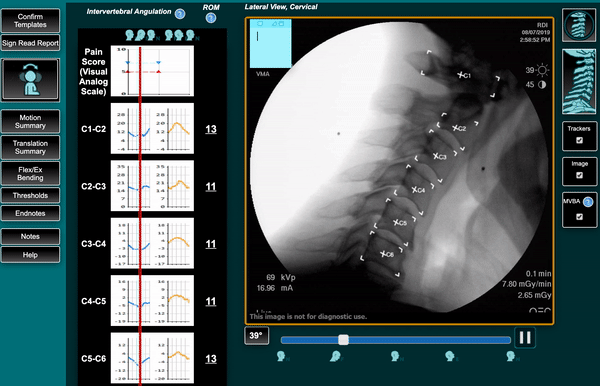

Vertebral Motion Analysis, or VMA®, is an FDA-cleared motion-based spine diagnostic that shows how the spine behaves in real time. Instead of taking still pictures like standard X-rays or MRIs, VMA captures continuous imaging as the patient gently bends forward, backward, and side to side.

Using a surgical-grade C-arm and proprietary software, VMA measures the movement of each vertebra with sub-millimeter accuracy. This reveals spinal ligament injuries and mechanical instability that are invisible on imaging at rest.

A surgical C-arm takes continuous images at eight frames per second throughout the bending cycle.

Quantitative Motion Analysis

Specialized software tracks and measures:

- Vertebral translation (sliding)

- Angular rotation

- Excessive motion patterns

- Segmental instability

- Motion asymmetry

- Abnormal load distribution

- Measurements are accurate within 0.5–0.7 mm, far beyond the sensitivity of standard imaging.